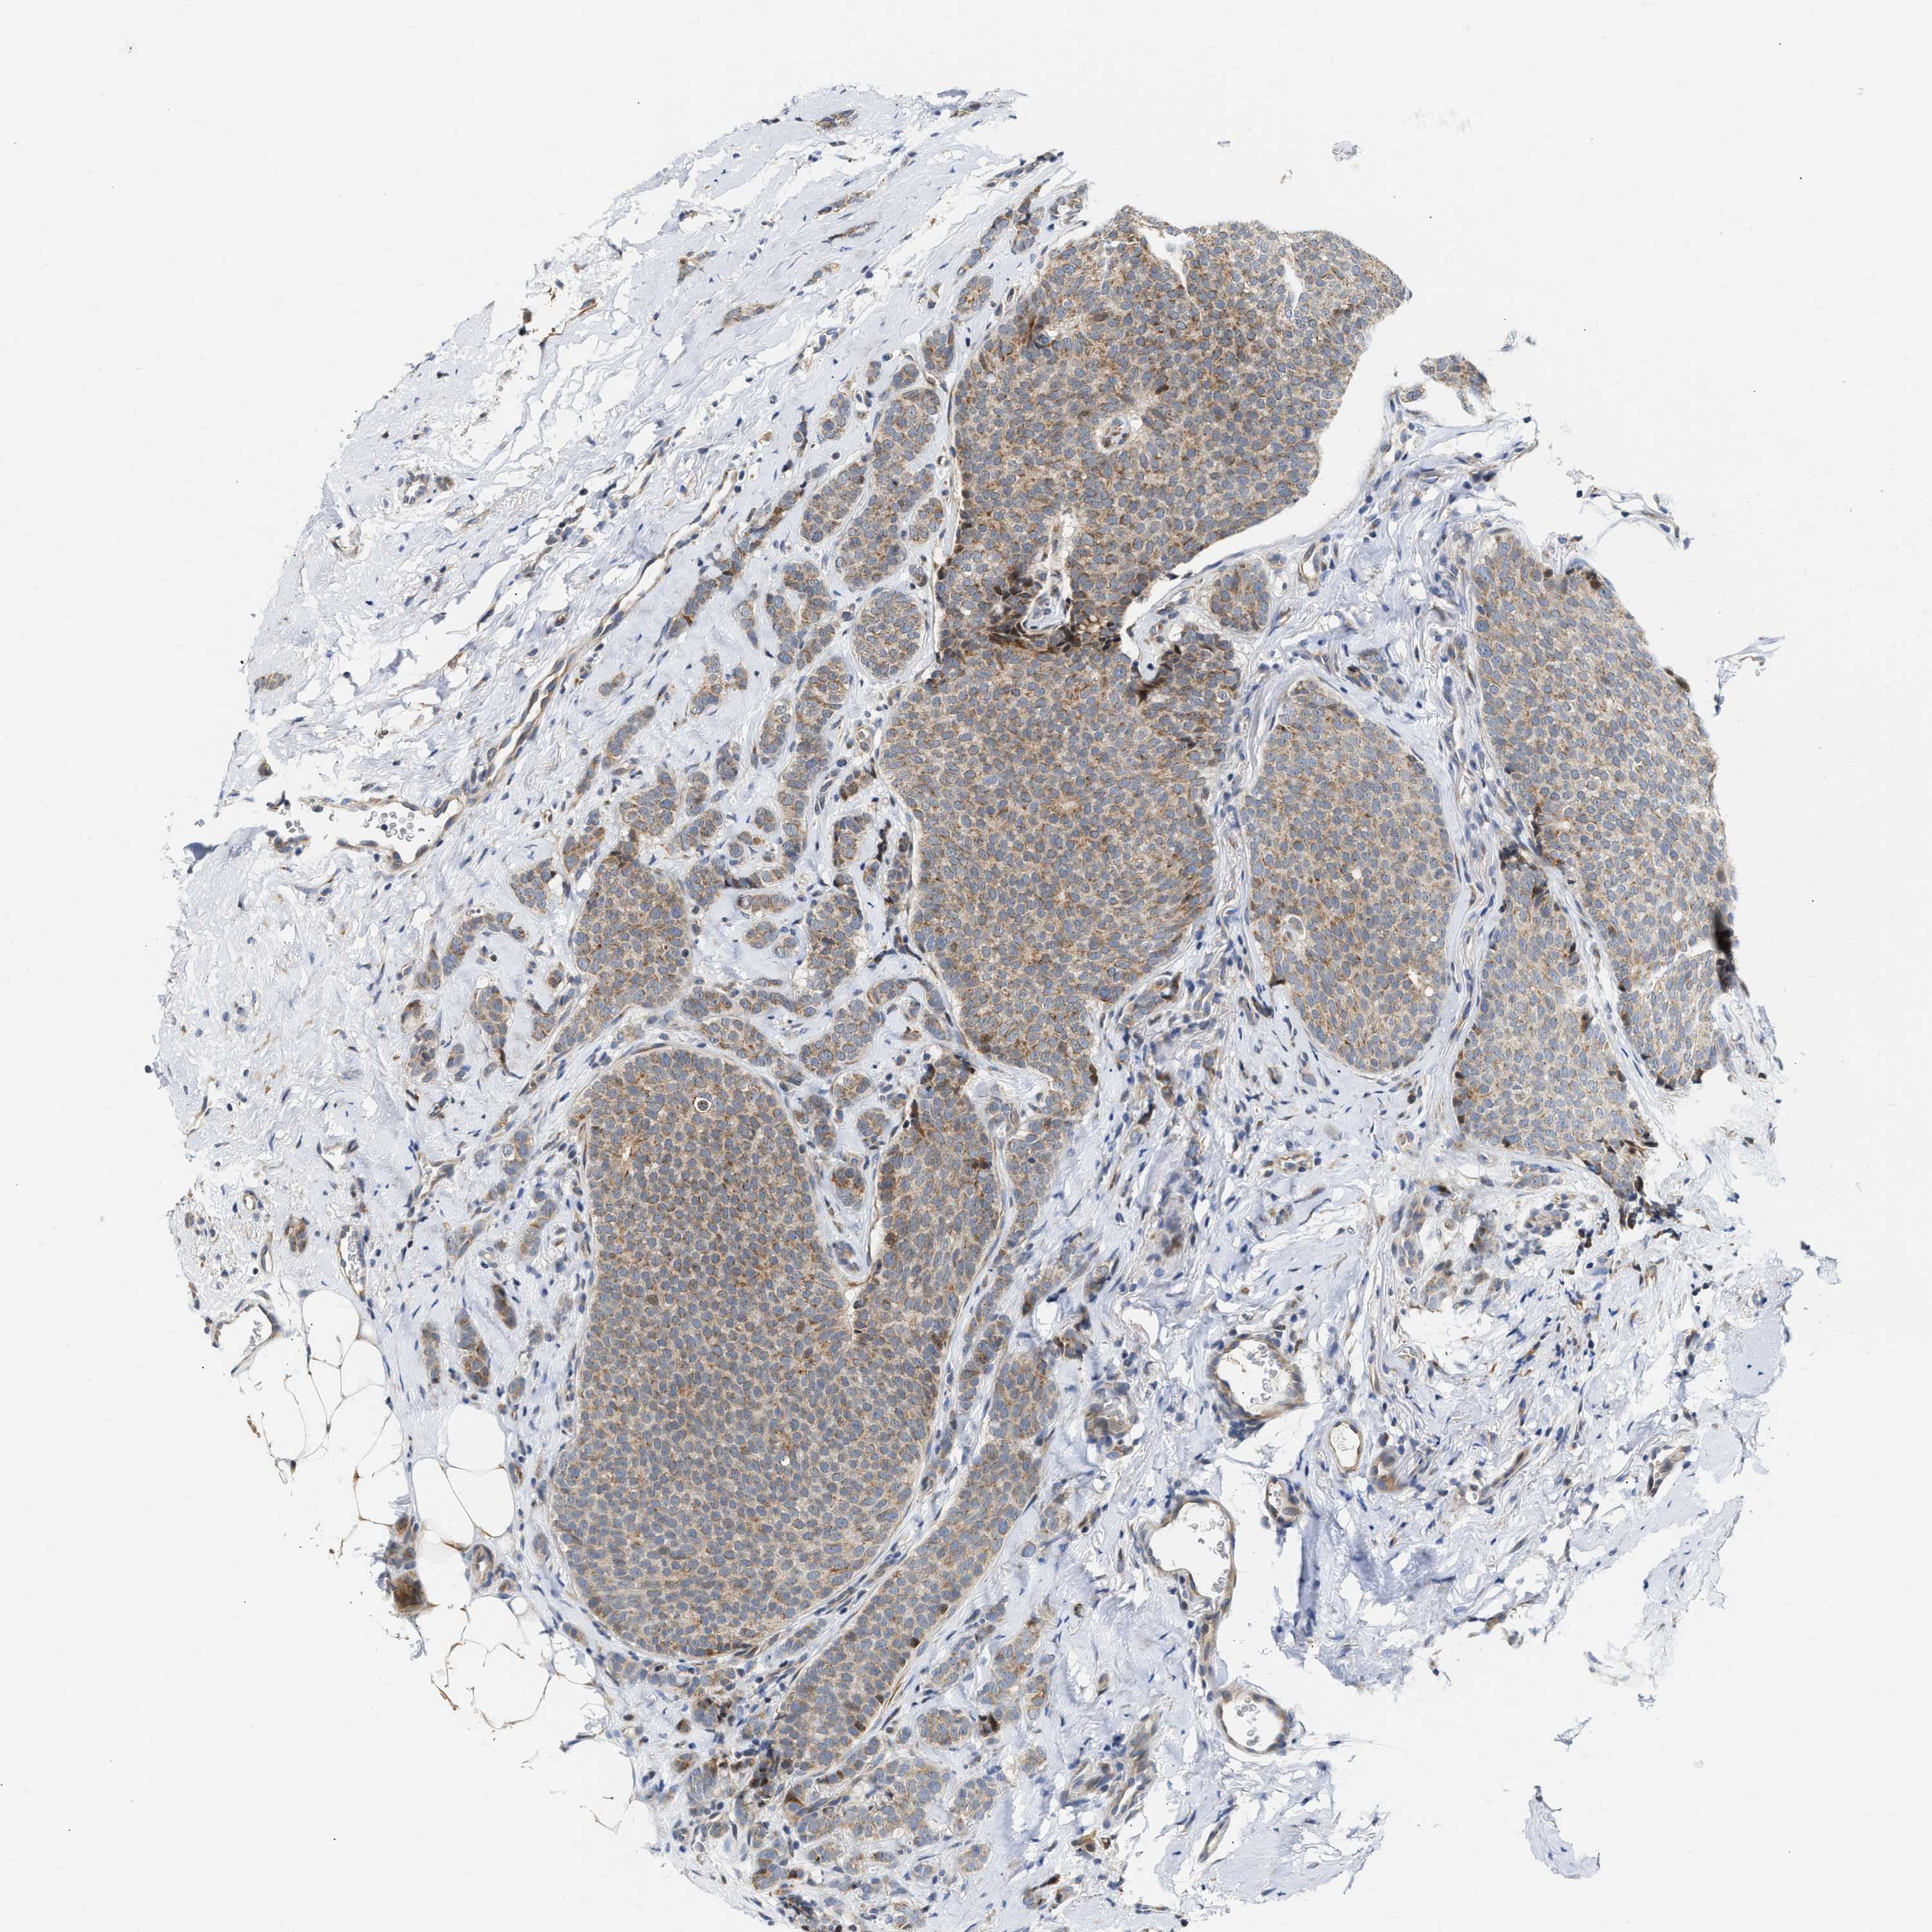

BRCA TCGA BRCA VALIDATION PROTEIN EXPRESSION